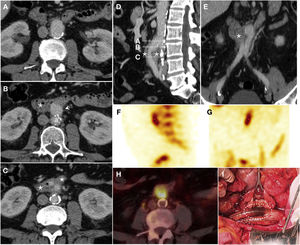

Secondary ileoenteric fistula in a 93-year-old male, with a history of aortobifemoral bypass surgery, who sought care as he presented coffee ground vomitus and melaena. Intravenous contrast was not administered due to a decreased glomerular filtration rate. Craniocaudal slices on the axial plane (A, B and C) of the aortobifemoral bypass (arrow tip) anterior to the native aorta (a) are shown. Figure C identifies intraluminal gas in the right branch of the bypass (arrow) from the immediately adjacent intestinal loop; the native iliac artery is indicated as an anatomical reference (i). Sagittal reconstruction (D) represents the level of the slices.

Primary aorto-oesophageal fistula in a 67-year-old male with haematemesis, profuse sweating, skin pallor and hypotension. Baseline computed tomography (A) showed oesophageal dilatation with intraluminal content of high attenuation in relation to a blood component (*) and displacement of intimal calcifications indicating rupture of an atheromatous plaque with an entrance (arrow). The arterial phase on the axial plane (B), sagittal reconstruction (C) and volumetric reconstruction (D) showed calcifications in the wall of the descending aorta and saccular dilatation (arrow tip) in contact with the oesophageal wall with no fat plane achieving separation. These findings suggested a penetrating ulcer. Despite the absence of extravasation of intravenous contrast, the presence of an aortoenteric fistula was confirmed in surgery.

Primary aortoduodenal fistula in a 65-year-old male with an episode of intermittent vomiting and melaena for the past 2 weeks who visited the emergency department with haematemesis, dizziness and hypotension. Baseline computed tomography (A and B) demonstrated high-density (47 HU) content in the gastric chamber in relation to a clot and a calcified aneurysm in the abdominal aorta with an intramural haematoma. The arterial phase (C) revealed a saccular bulge on the anterolateral aspect of the aorta with loss of the fat plane achieving separation with the duodenum (*). The late phase (D) did not demonstrate clear extravasation of IVC. Laparoscopy confirmed the presence of an AEF (E) (a: aorta; d: duodenum; f: fistula) which was repaired in the same surgical procedure (F) including segmental resection of the duodenum.

Graft erosion in a 61-year-old male with a history of aortobifemoral bypass surgery who presented long-standing fever, chills, weakness and persistent bacteraemia. Due to suspicion of graft infection, a CT scan was performed with IVC in the portal phase (A–C) which revealed perigraft oedema and parietal thickening of the third segment of the duodenum (*) encompassing the right iliac branch of the bypass in the absence of a fat plane achieving separation. Sagittal reconstruction (D) represented the level of the axial slices and coronal reconstruction (E) supported the findings reported. Extravasation of IVC was not observed. SPECT with marked leukocytes (F, G) showed radiotracer accumulation, and a PET/CT scan (H) revealed an increase in metabolic activity in the region proximal to the graft. These findings were suggestive of infection. Surgery (I) demonstrated the presence of graft erosion (dashed ellipse).